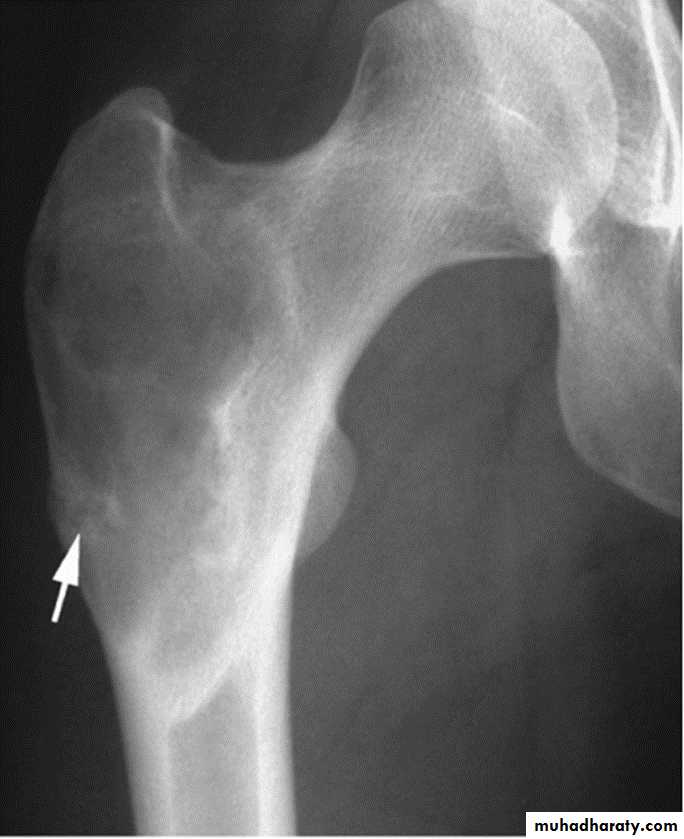

Fibrous dysplasia.

AP radiograph of the proximal femur showing a well-defined expanded lesion with typical ground-glass matrix mineralization and a thick, sclerotic margin .Fibrous dysplasia.

A multilocular, partly cystic, expansile lesion

of the midshaft femur is surrounded by a thick rim of reactive sclerosis.